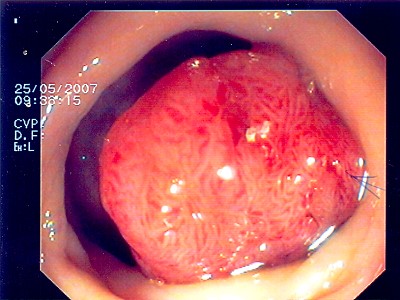

Noch gutartiges Gebilde des Mastdarmes mit schweren Zell- veränderungen. Hier ist eine den Schließmuskel erhaltende Operation möglich - transanale mikroskopische Tumorentfernung (TEM).